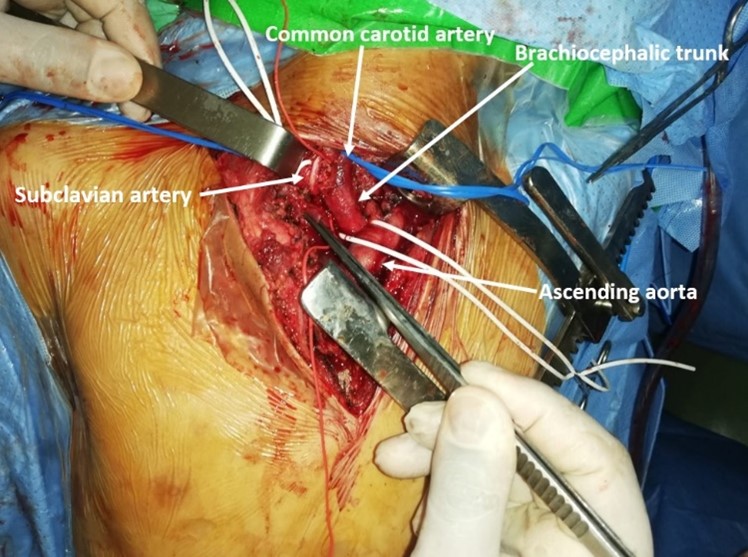

The decision was to perform open surgery in collaboration with thoracic surgeons. The child was admitted to the operating room: After monitoring and conditioning, the child was installed in dorsal decubitus, under general anesthesia: After a mini-sternotomy approach combined with a right infraclavicular incision, primary control of the brachiocephalic arterial trunk and the right common carotid artery. The exploration showed a false aneurysm of the SCA, with a breach near the origin of the common carotid artery (Figure 3). After general heparinization, clamping of the brachiocephalic arterial trunk, the common carotid artery and the distal SCA, we perform a closure of the breach with separate stitches of 5/0 prolene (Figure 4).

Figure 3: Intraoperative photograph showing the breach of SCA near the origin of the common carotid artery (arrow).